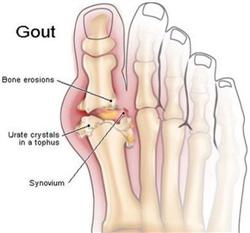

Gout is a disease caused by the faulty metabolism of purine in the body. It is a common type of arthritis, in which tiny crystals are formed in and around joints. Its clinical features include arthritis which usually attacks repeatedly, deformed joints, and the formation of uric acid stones or gouty stones.

Gout is a disease caused by the faulty metabolism of purine in the body. It is a common type of arthritis, in which tiny crystals are formed in and around joints. Its clinical features include arthritis which usually attacks repeatedly, deformed joints, and the formation of uric acid stones or gouty stones.The disease is rare in people under the age of 30. Men are more likely to develop gout than women because their uric acid levels rise during puberty. about 95 percent of sufferers are men. It is believed that genetic predisposition is the most common reason for gout to occur. Gout is relative to the high level of uric acid in the blood which is the result of excessive formation or the decrease of excretion by chronic kidney, blood or cardiovascular diseases. Eating too much food with high levels of purine and drinking too much beer or spirits may precipitate individual attacks. Certain medications, such as some types of diuretics, aspirin and niacin can also cause gout.

In treating gout one must control their diet to prevent becoming overweight. Do not take too much food with high levels of purine, such as animal’s internal organs, fish roe and sardines. Alcohol consumption must also be avoided; catching colds, fatigue, nervousness and damaging the joints should also be avoided. Drink plenty of water to make sure that the daily urine exceeds 2000mL. This will help with the excretion of uric acid. During the acute attack of arthritis, you should have more rest.